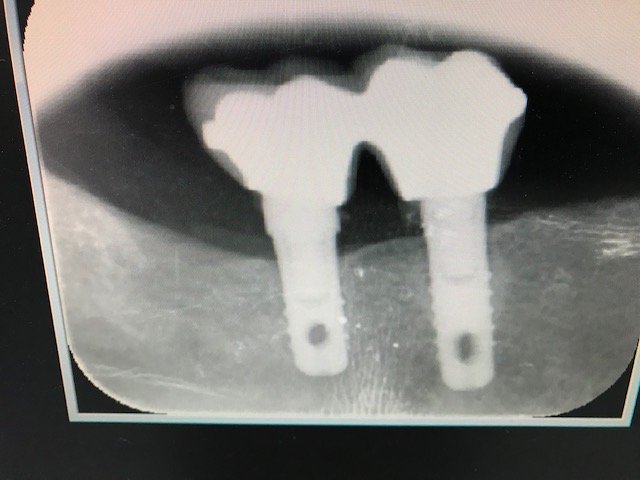

Buenos días colegas, me podrían colaborar con la marca de los implantes del cuadrante I. Podran ser alpha bio?? Muchas gracias

Como cirujano de una de la clinicas que colaboro me mandan esta rx para determinar que implantes lleva en el primer cuadrante para poder realizar la rehabilitacion protesica de nuevo.